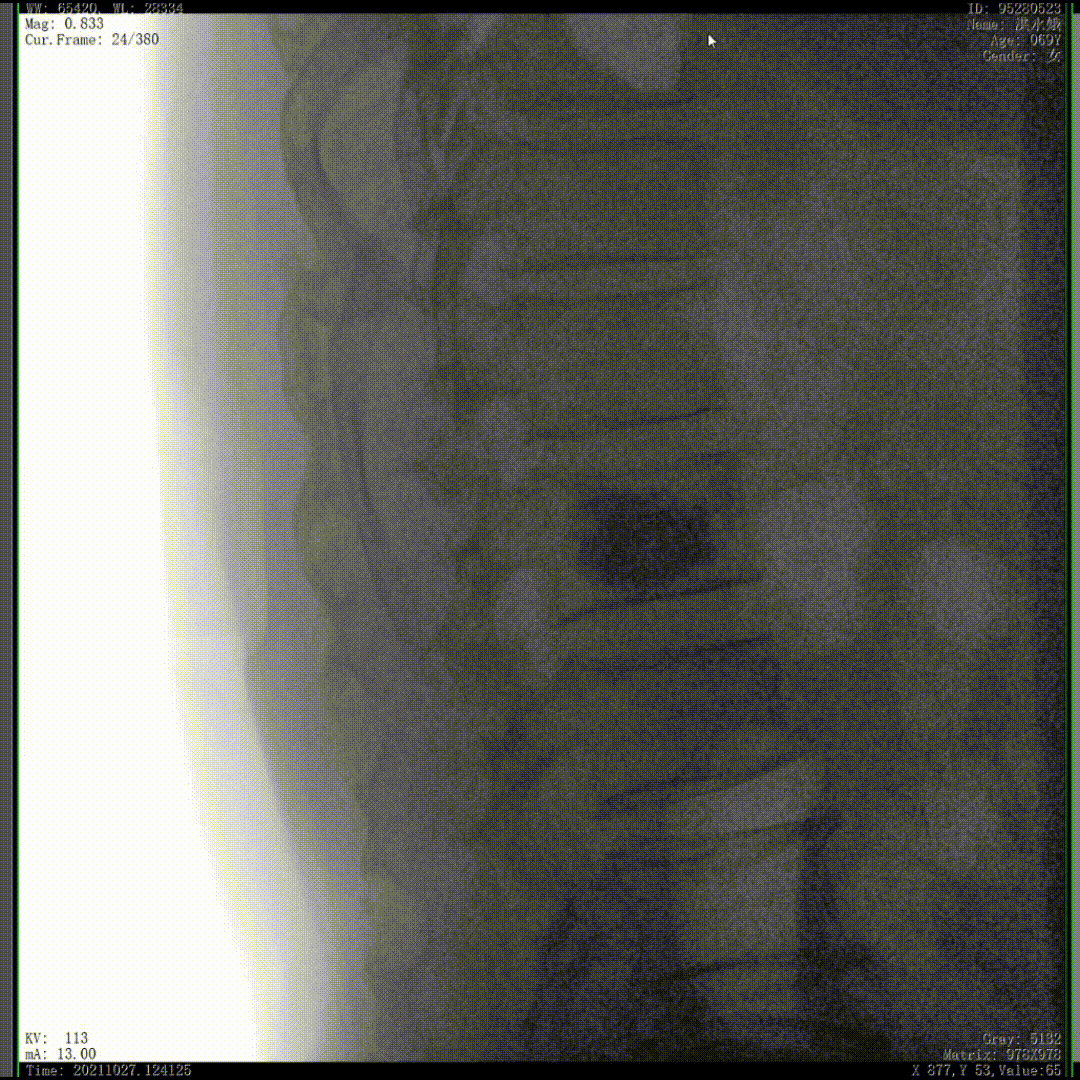

我們完成了椎體成形術(shù)以后,在二維的正側(cè)位影像上還不能看清骨水泥的滲漏情況,通過三維影像就可以360°的觀察骨水泥在椎體里到底是怎么彌散的。如果當(dāng)時我們判斷出來質(zhì)量不好,可能還需要進(jìn)行翻修,這是在二維影像上不能看到的。